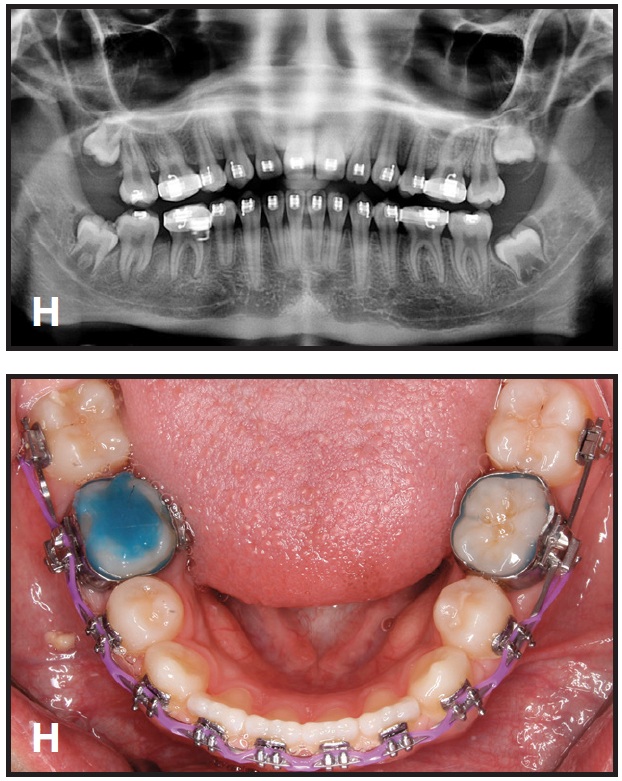

This technique is demonstrated in a 13-year-old female patient with an impacted lower right second molar (D). A U-loop spring was activated after surgical exposure of the tooth (E). Two months later, the second molar had been partially uprighted (F). After three more months of uprighting, the spring was removed and a continuous archwire was placed (G). It took another three months to completely upright the molar using straightwire mechanics, with no side effects on the anchor units (H).